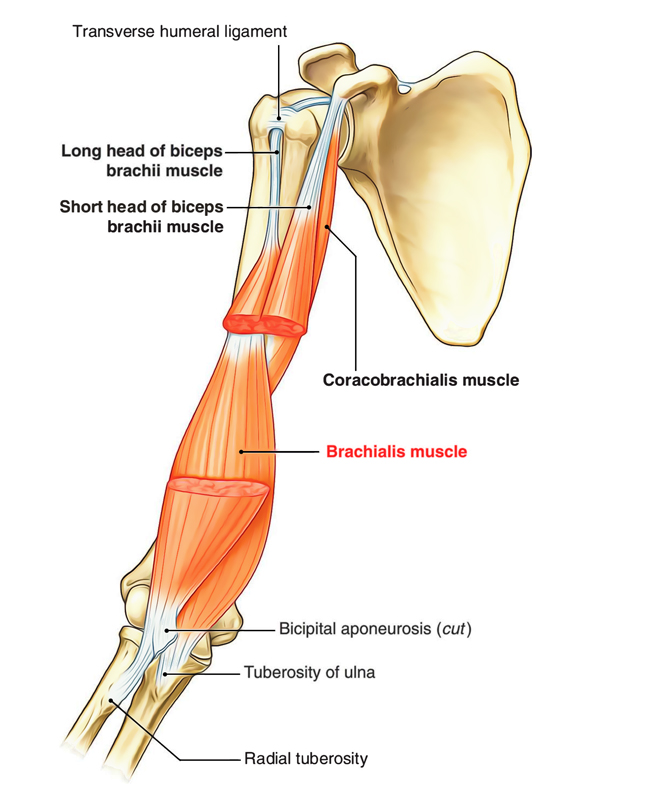

Анатомия и функции мышцы brachioradialis